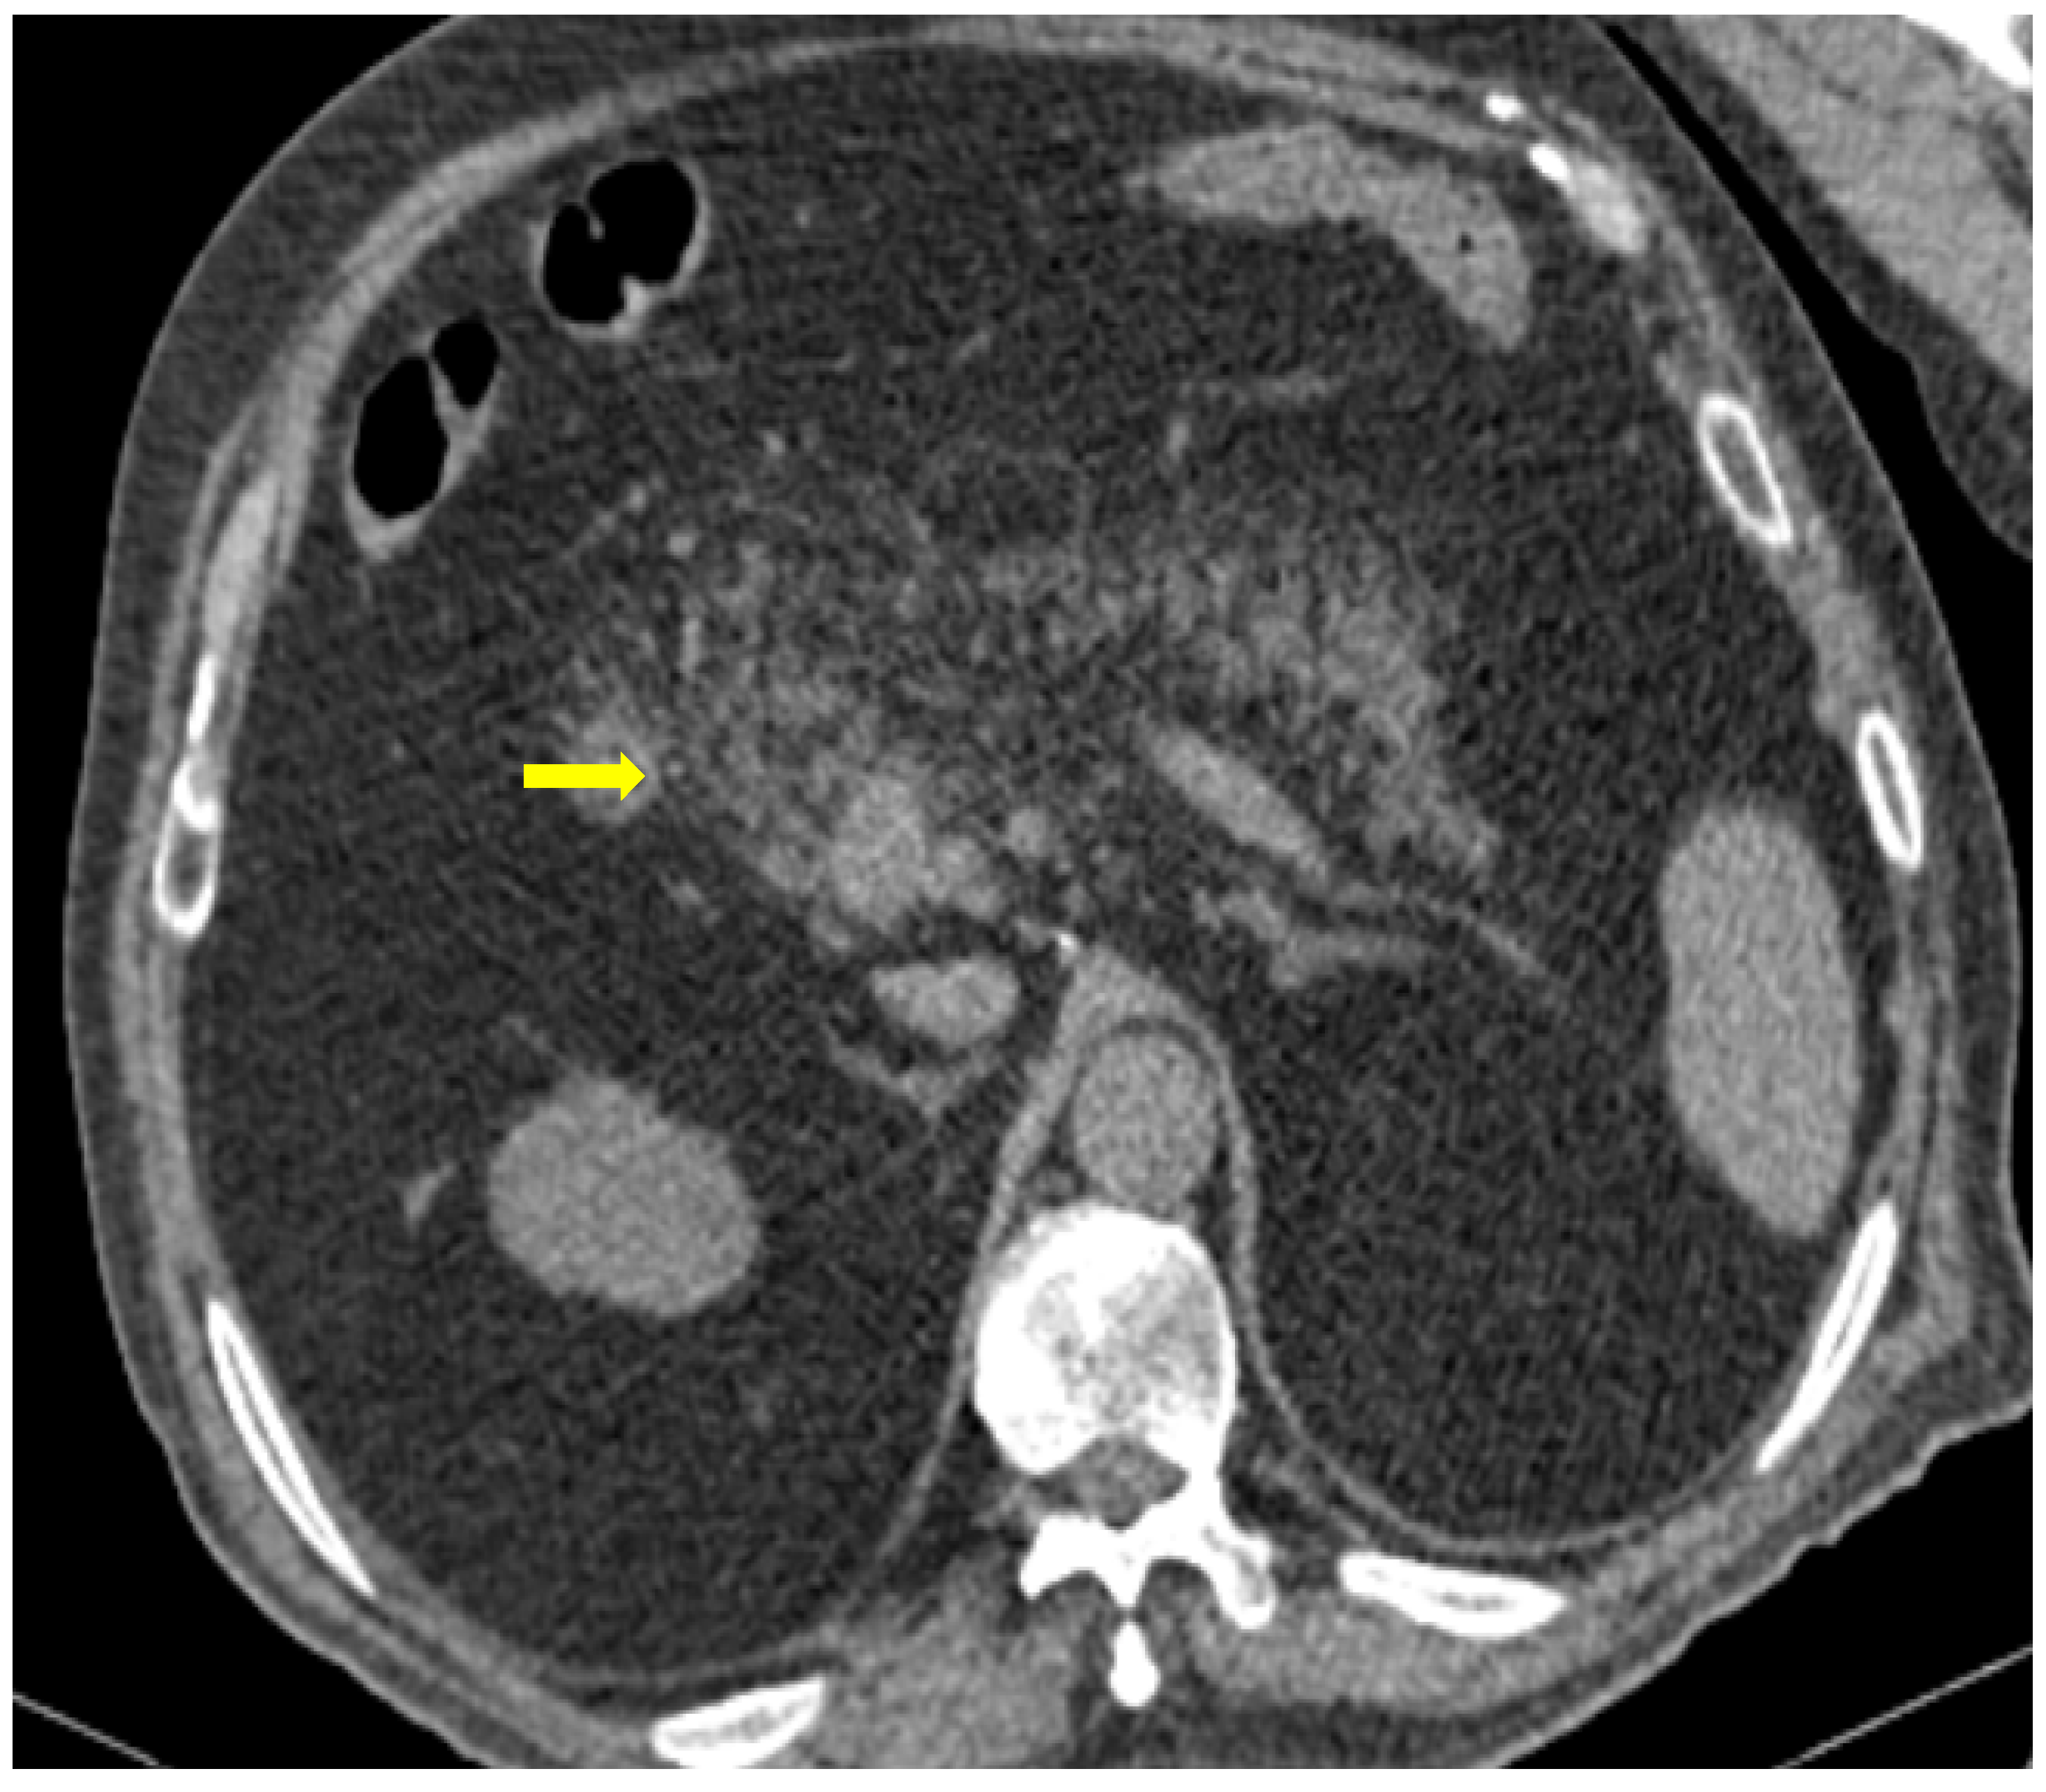

Figure 9. 81-year-old patient with COVID-19 pneumonia developed epigastric pain at the second day of hospitalization. CT demonstrating acute pancreatitis (yellow arrow).